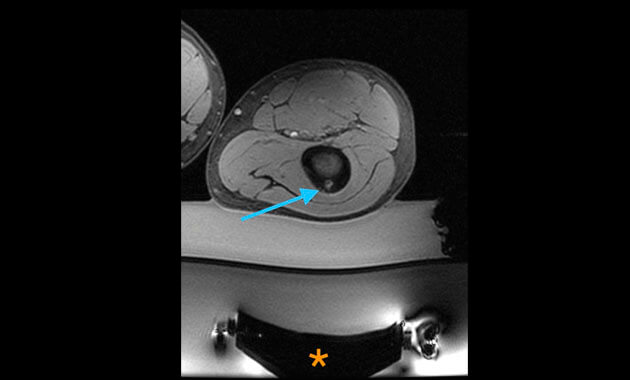

Osteoid osteomas are painful bone tumors and make up about 10 percent of all benign bone tumors. They are most common in patients under the age of 25, particularly adolescents, with males affected three times more often than females.

Osteoid osteomas produce pain which is typically most severe at night and relieved by non-steroidal anti-inflammatory medications such as ibuprofen. When pain begins to significantly interfere with activities of daily living despite medication, or if severe symptoms persist, many patients are referred for a minimally invasive procedure to treat the tumor.